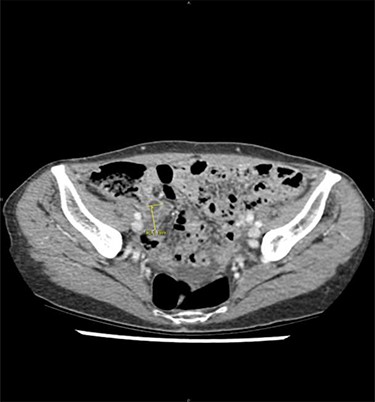

After refusing any anticancer treatment therapy, the patient died 1 year after appendicectomy. By retrospectively analysing imaging performed at the emergency department, we observe that the nodules of peritoneal carcinomatosis could be identifiable on CT images (Fig. 2).

Peritoneal noduli observed after retrospective analysis of abdominal computed tomodensitometry (yellow arrow).